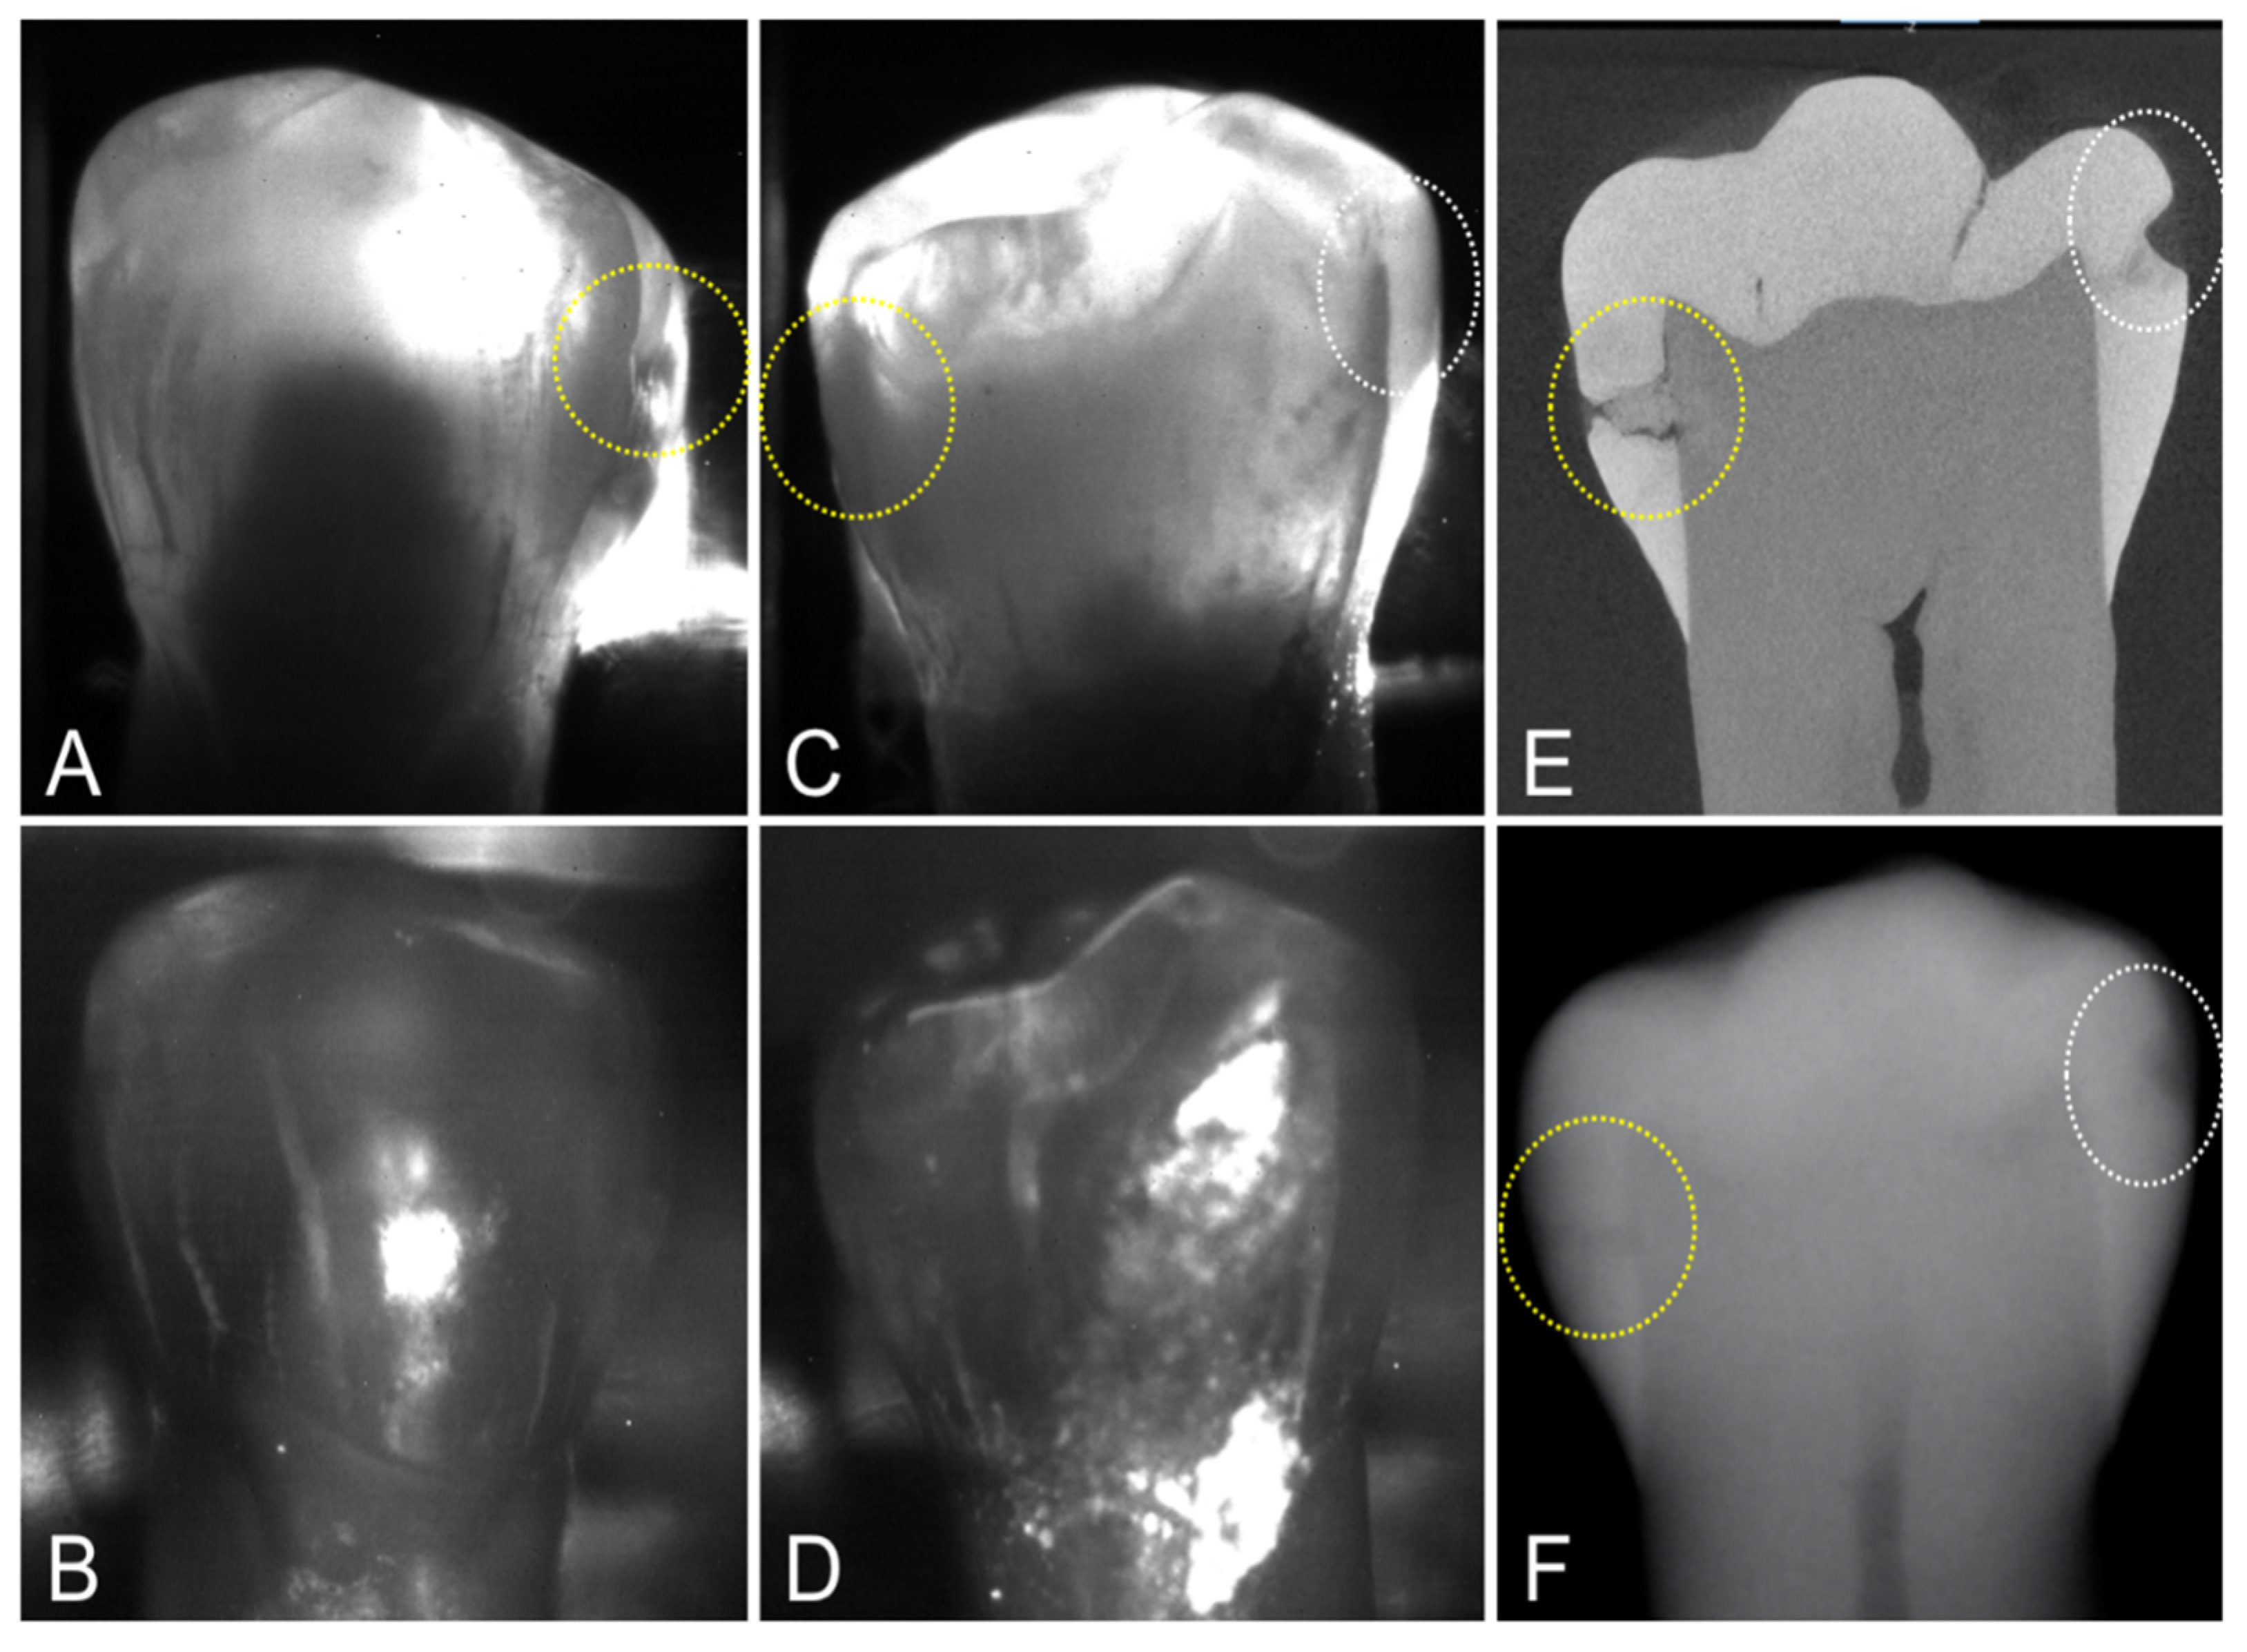

MicroCT was used to image the 36 extracted teeth used for this study. There were 67 lesions visible on microCT images indicating that most of the teeth had lesions at both contact points (mesial and distal sides), i.e., 67 out of a possible 72 if lesions were present at all contact points, two per tooth. Out of the 67 lesions, 16 of the lesions were very small and were only visible with microCT. Only 22 of the 67 lesions had measurable contrast on dental radiographs for a detection rate of only 33%. Proximal transillumination at 1300 nm performed well showing measurable contrast for 40 out of 67 lesions, giving a 60% lesion detection rate. The lesion contrast was high for most proximal transillumination images, however, only seven of the lesions were visible in the proximal reflectance images of the buccal and lingual surfaces. There are two interproximal lesions on the tooth shown in Figure 3, one is deep and penetrates into the dentin while the second lesion is shallow and only penetrates halfway through the enamel. Both lesions are visible in the radiograph. Both lesions show significant contrast in the proximal transillumination mode. When imaged from the lingual side, Figure 3C, both lesions are visible, however only one of the lesions is visible when the imager was positioned on the buccal side of the tooth, Figure 3A. However, the two lesions are not visible in the corresponding reflectance images shown in Figure 3B,D, neither from the lingual nor from the buccal surface. Both lesions are clearly visible in the microCT image shown in Figure 3E.

Figure 3. Proximal transillumination and reflectance images of a tooth with two interproximal lesions on opposing proximal surfaces. Lesion 1 (yellow circle) is more severe and penetrates to the dentin while lesion 2 (white circle) is limited to the enamel. (A) Transillumination and (B) Reflectance images with the imager on the buccal side of the tooth. (C) Transillumination and (D) Reflectance with the imager on the lingual side of the tooth. (E) MicroCT slice (F) and Dental X-Radiograph are also shown. Neither lesion is visible in the proximal reflectance images.